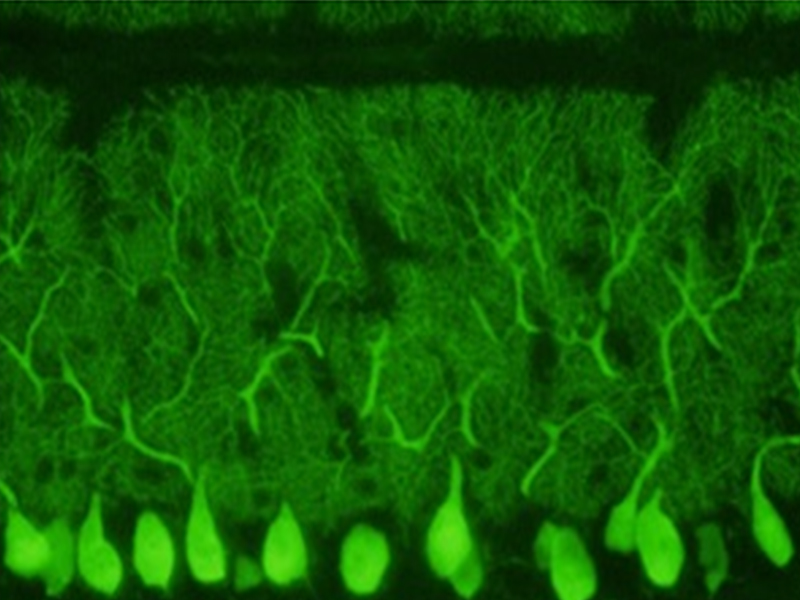

抗体开发革命:通过全链路创新将研发周期缩短60%,创下"18天从免疫致敏到抗体获得"的行业纪录,并建成标准化抗体细胞库;

纳米医学突破:在靶向药物递送、肿瘤微环境调控等领域实现多项国内空白技术攻关。